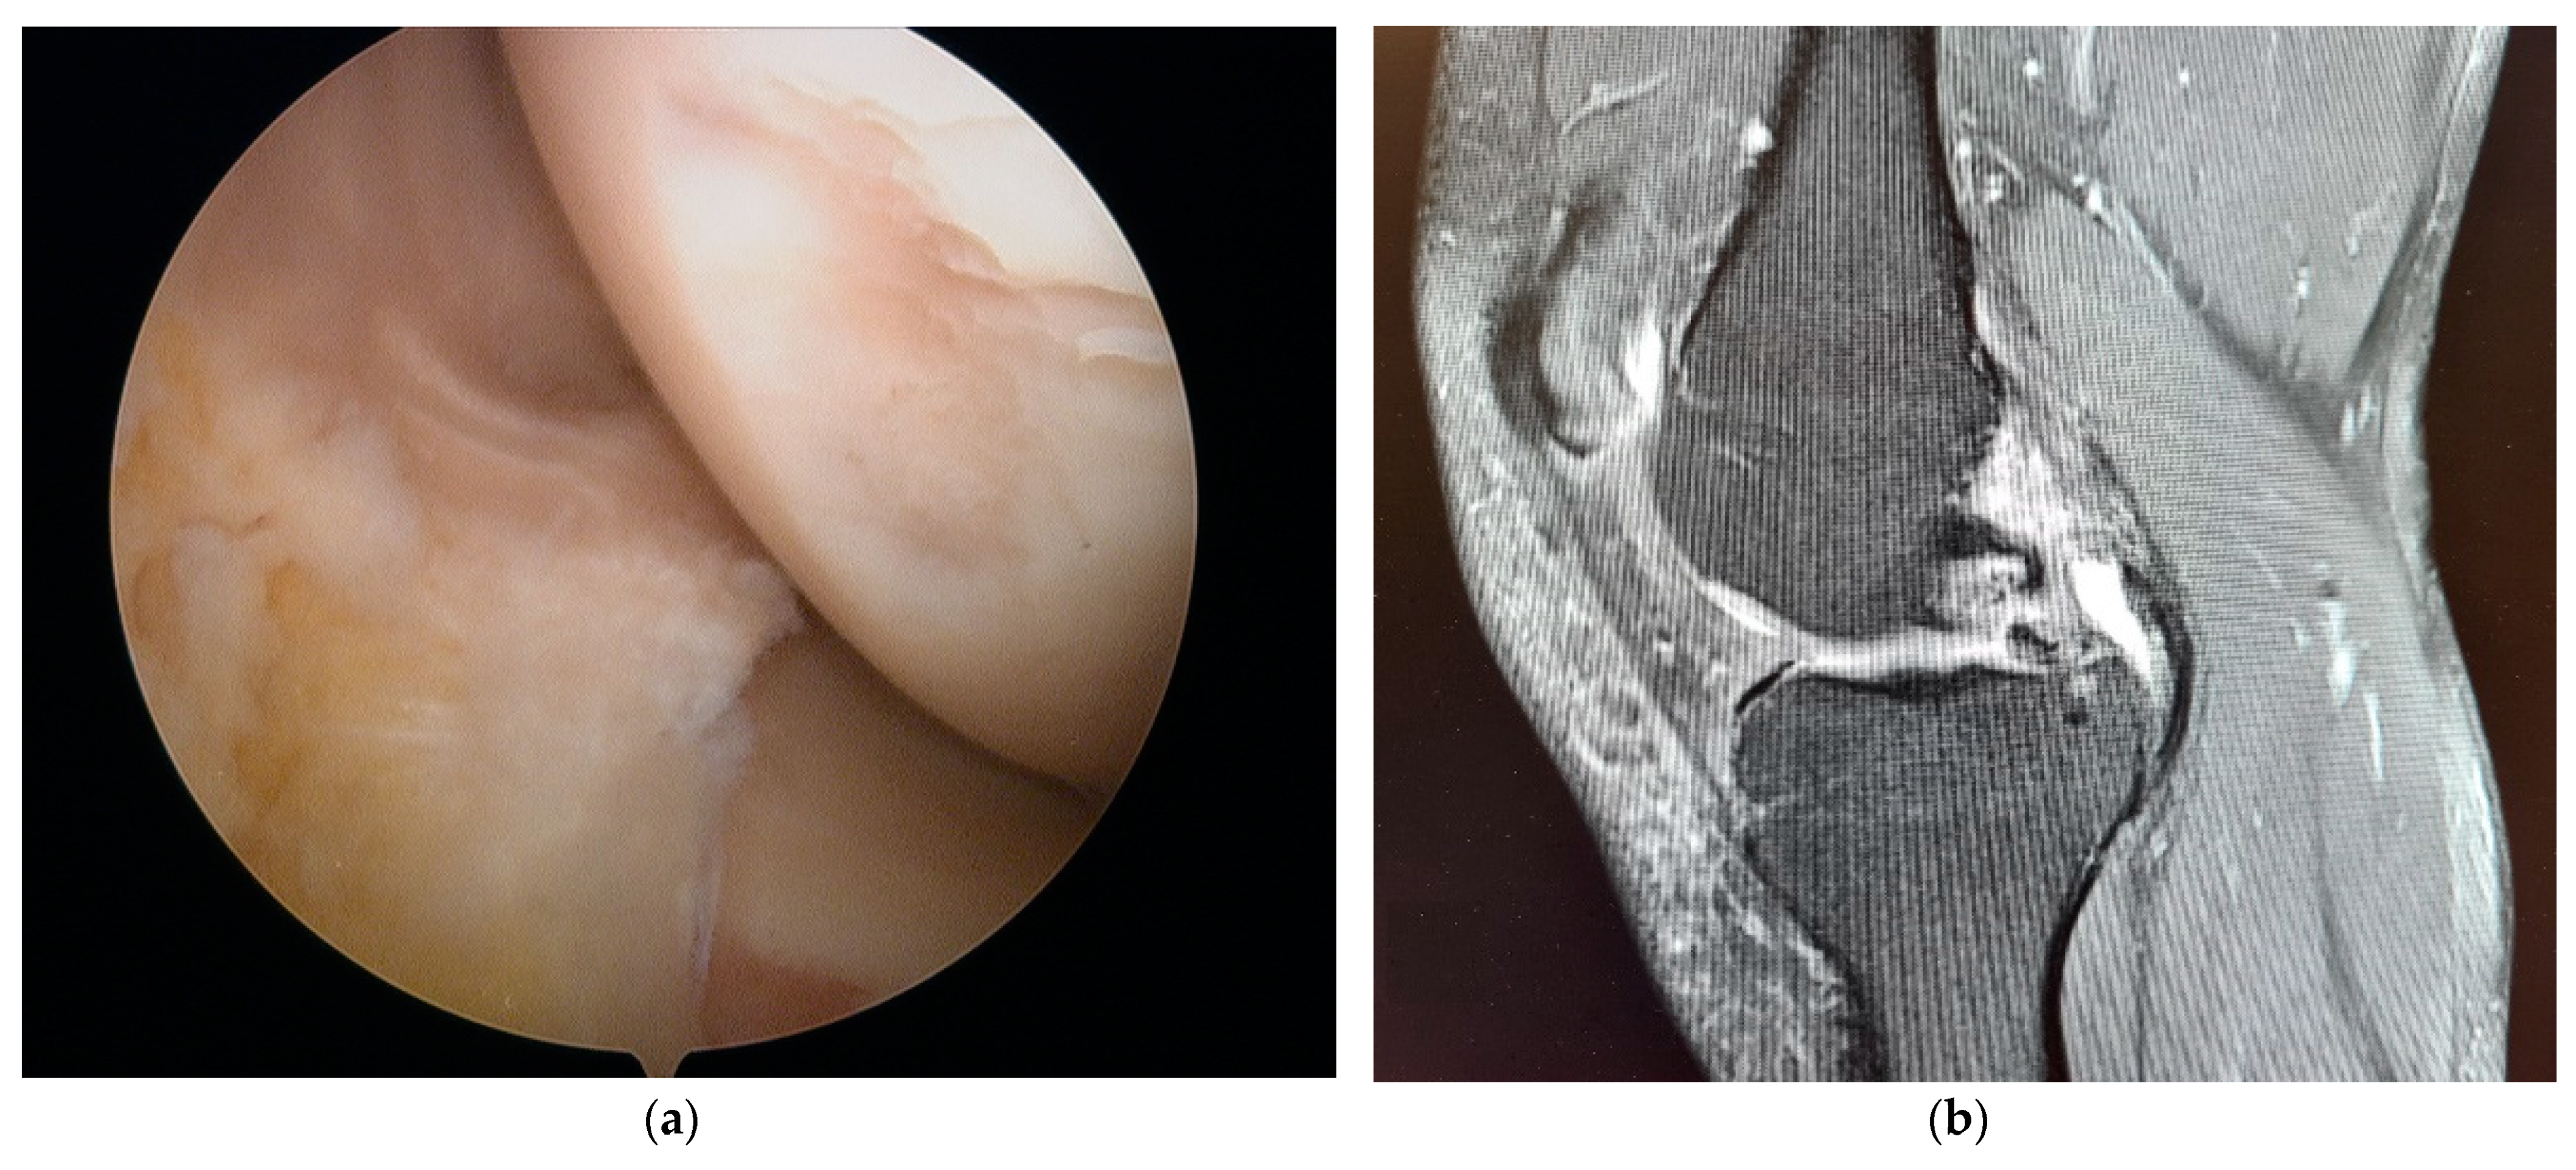

2. Materials and Methods

3. Results

4. Discussion